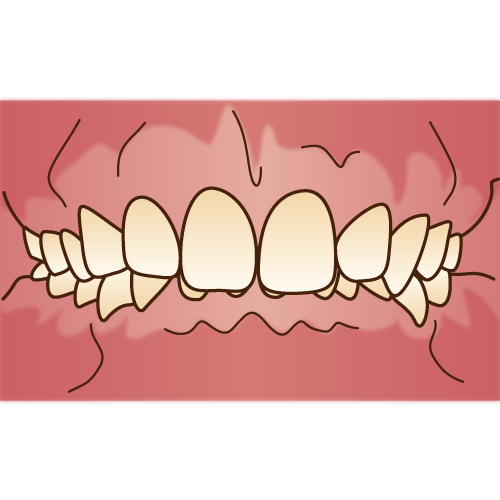

歯並びが悪いと、磨き残しが残りやすくなり、虫歯や歯周病になりやすくなり、噛み合わせが悪いと、歯や顎関節に負担がかかります。

矯正治療を受けたい最初の動機は、見た目の改善だとしても、矯正治療を受けることで、歯並びや噛み合わせが良くなり、結果的に上述したような、虫歯や歯周病のリスクの軽減、歯や顎関節の負担も軽減も出来ます。

また、歯並びや噛み合わせが良くなることで、発音がしやすくなったり、食事がしやすくなる可能性もあります。